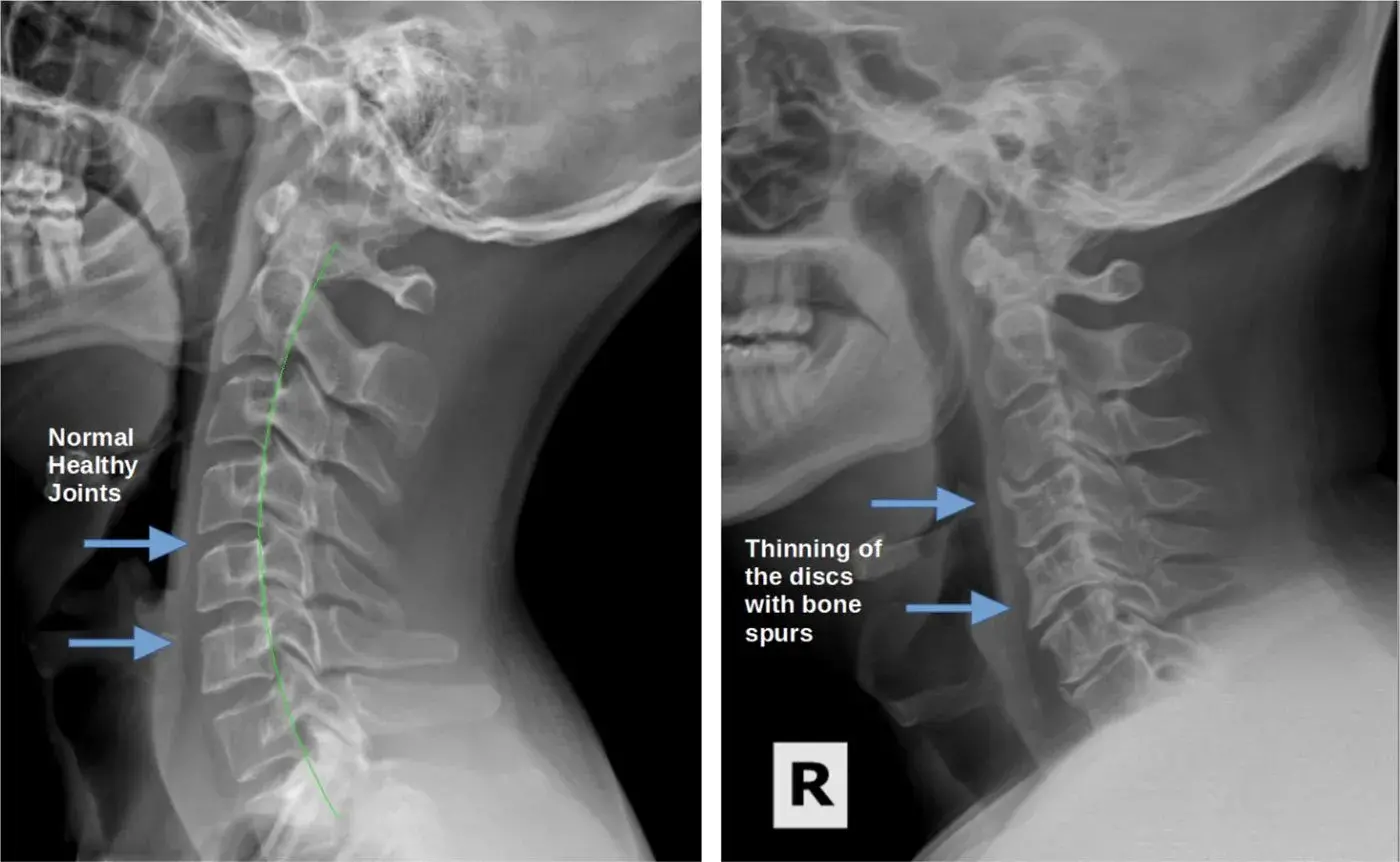

• Degenerative Disc Disease: WWith age, the cervical discs can undergo degenerative changes, leading to wear and tear. This can cause chronic neck pain, stiffness, reduced flexibility, and even nerve compression. Effective management involves pain medication, physical therapy, targeted exercises, posture correction, and beneficial lifestyle modifications. Regular stretching and ergonomic adjustments can provide additional relief and support.